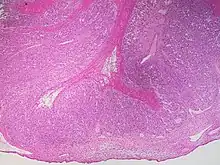

This type of functional cyst occurs after an egg has been released from a follicle. The follicle then becomes a secretory gland that is known as the corpus luteum. The ruptured follicle begins producing large quantities of estrogen and progesterone in preparation for conception. If a pregnancy doesn't occur, the corpus luteum usually breaks down and disappears. It may, however, fill with fluid or blood, causing the corpus luteum to expand into a cyst, and stay in the ovary. Usually, this cyst is on only one side, and does not produce any symptoms.[1][2]